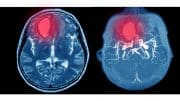

Summary Mild traumatic brain injury is a clinical syndrome caused by direct or indirect head trauma, classified with a Glasgow Coma Scale of 13-15. It…